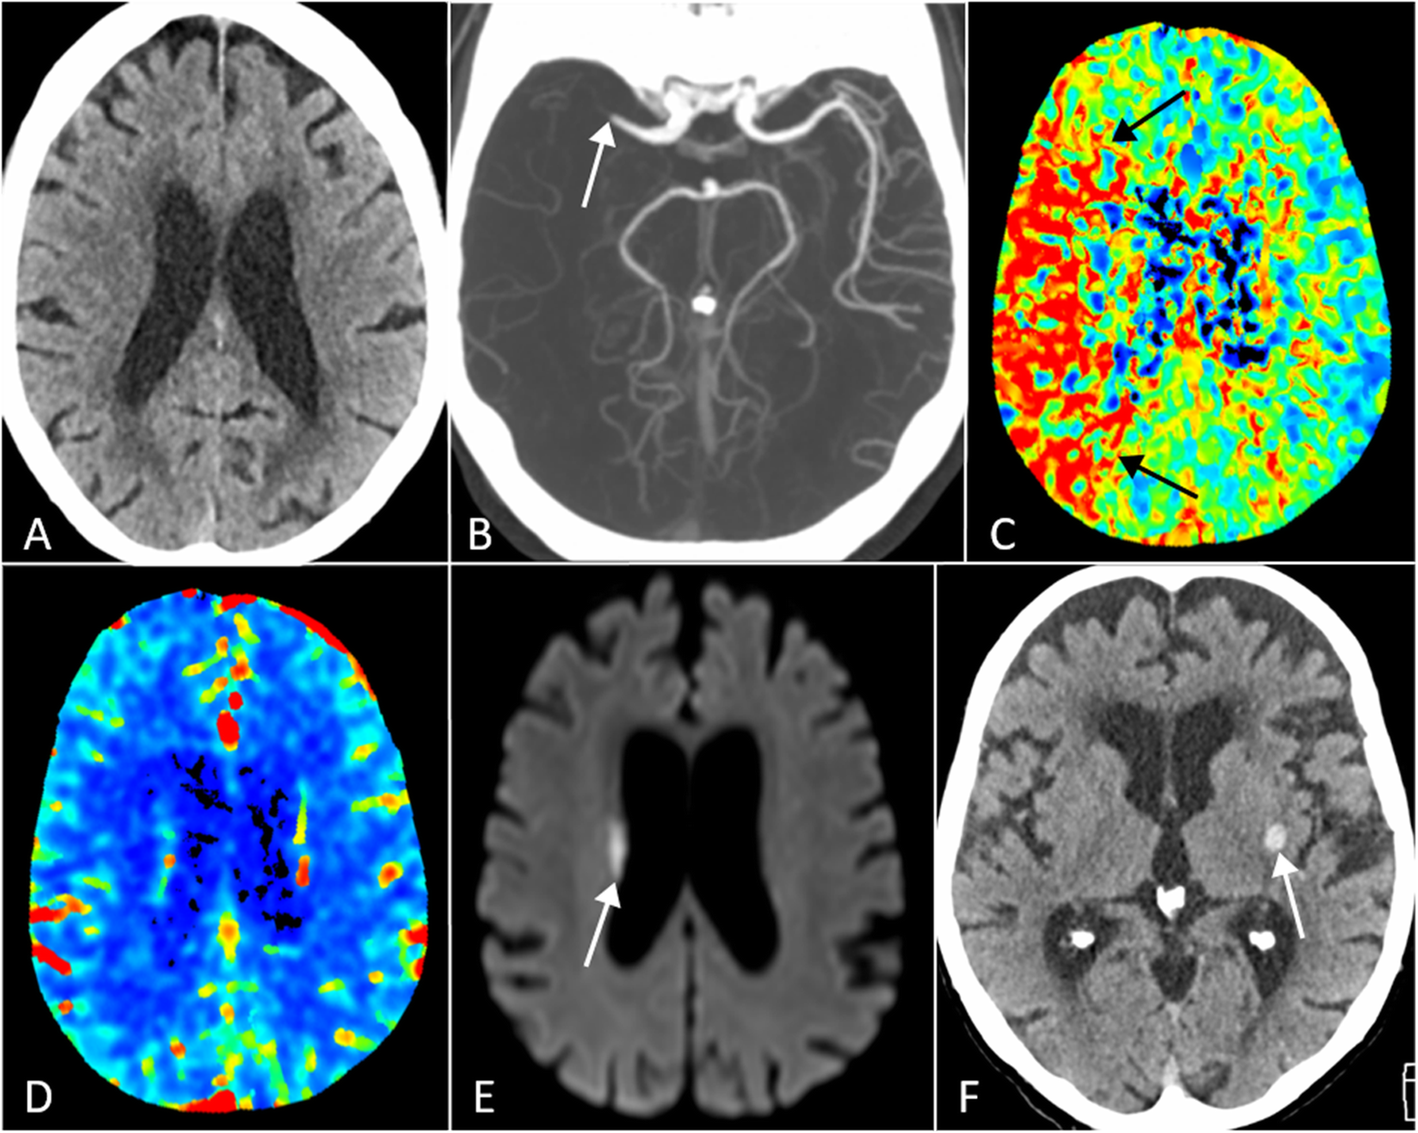

Fig. 1

Illustrative images of neurologic complications in older patients hospitalized with COVID-19 pneumonia. a, b, c, d, and e, CT and MRI images of an 89-year-old woman with left-sided hemiplegia. a, Non-contrast head CT did not show early CT signs of ischemia. b, CT angiogram showed occlusion of the right middle cerebral artery (arrow). c, Perfusion CT mean transit time (MTT) images showed prolonged MTT in the entire right middle cerebral artery territory (arrows), whereas perfusion CT derived cerebral blood volume (d) remained symmetric between both hemispheres. e, Diffusion-weighted image of MRI study obtained one day later and after intravenous thrombolysis showed a small area of infarction in the right corona radiata (arrow). f, Non-contrast head CT image of an 84-year-old woman with obnubilation showed an isolated focus of intraparenchymal hemorrhage in the left lentiform nucleus (arrow). No evidence of underlying vascular or tumoral pathology was found on subsequent MRI (not shown)